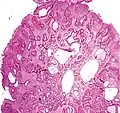

Micrograph of a Peutz–Jeghers colonic polyp – a type of hamartomatous polyp. H&E stain.